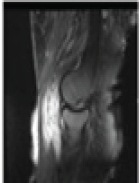

Magnetic resonance imaging (MRI) revealed an ill-defined lobulated lesion measuring 10 × 9 × 6 cm involving the synovium, intra-articular and periarticular tissues of the postero-lateral elbow, producing erosions of the distal humerus and proximal radius and ulna, with distortion of joint alignment, radiologically mimicking synovial chondromatosis (Fig. 3).

Figure 3: Magnetic resonance imaging revealed an ill-defined lobulated lesion measuring 10 × 9 × 6 cm involving the synovium, intra-articular, and periarticular tissues of the postero-lateral elbow.